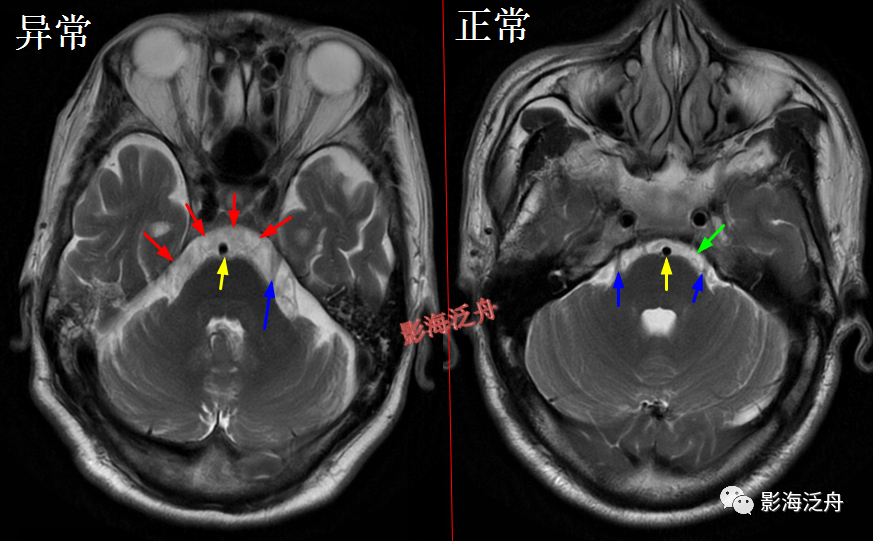

颞极前方蛛网膜囊肿(红箭)漏诊率也比较高,尤其在老年患者中,常常被误认为是扩大的蛛网膜下间隙,仔细观察可以发现右侧颞叶受压,脑沟闭塞(绿箭),与健侧(蓝箭)对比更为明显。

这个烟雾病的病例在之前的文章中(颅脑MR平扫中极易漏诊的点!)已经提到过,再拿出来复习一下。

脑膜炎

患者,桥前池内可见异常增多的血管影(红箭),正常人的桥前池因为脑脊液流动产生的伪影也可以看到池内絮状低信号(绿箭),但不如右侧患者的明显,这个观察起来比较困难,就如在腹部CT

上观察患者是否存在肝脏肿大一样,需要一个经验积累的过程。黄

箭指基底动脉,蓝箭指三叉神经。